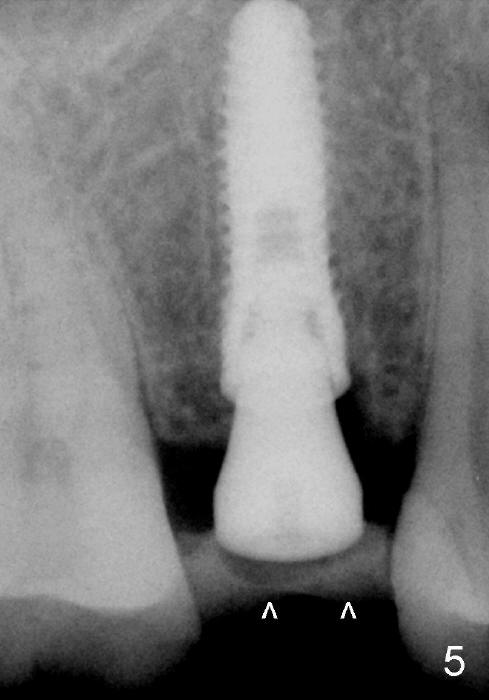

A 51-year-old man has several missing teeth in the maxilla restored by a partial denture. The tooth #4 fractures (Fig.1) and is planned to be restored by an implant (Fig.2 design: 4.5x14 mm). Immediately post extraction, osteotomy is initiated by a 2.0 mm pilot drill at the depth of 14 mm (3 mm into new bone, Fig.3). Finally a 4.5x14 mm SM (submerged) implant is placed with insertion of a 5.2x5(3) mm healing abutment (Fig.4). Mixture of autogenous bone and demineralized cortical allograft is placed in the gap between the buccal plate and the implant/abutment (Fig.6), covered by collagen membrane (Fig.7 M; P: partial denture). In fact the membrane is fixed between the implant and the healing abutment lingually. The wound is finally covered by perio dressing (Fig.5 ^). The patient returns 5 days postop. The perio dressing is removed unintentionally. It appears that the membrane has started to be resorbed (Fig.8).

Due to insurance termination, restoration has to be done 2 months post implantation. Both the soft (Fig.10 *) and hard (Fig.11) tissues heal normally. A cemented abutment is placed (Fig.12 A). Fig.13 is taken 5 months post cementation. There is no bone resorption.